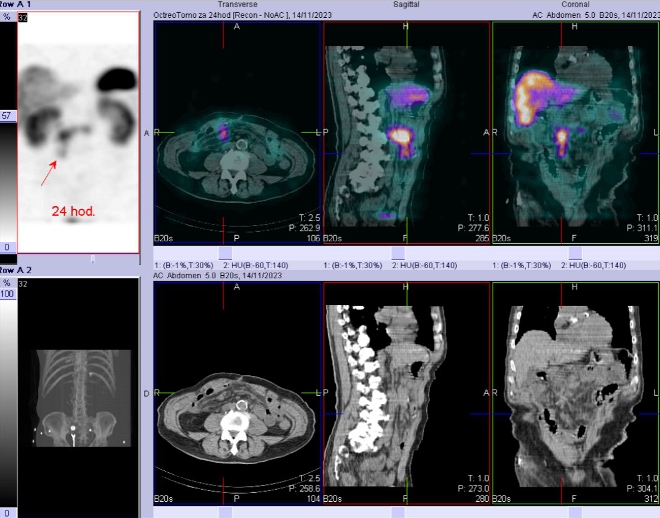

Scintigrafie Octreoscanem:

I. v. jsme aplikovali 190 MBq analogu somatostatinu značeného 111In

(přípravek OctreoScan firmy Mallinckrodt Medical) a provedli pomocí hybridní tomografické scintilační kamery Symbia T2 firmy Siemens opatřené kolimátory pro střední energie planární celotělovou scintigrafii a cílenou tomografickou scintigrafii (SPECT) břicha a pánve kombinovanou s CT za 4 a 24 hod.

(obr. 4-6).

/ Obr. č. 6: Fúze SPECT/CT břicha a pánve 24 hod. po aplikaci OctreoScanu.

Závěr: Prokazujeme tři okrsky patologicky zvýšené hustoty somatostatinových receptorů v paketu LU na mesenteriu vpravo ve výši L2, v LU v retroperitoneu paraortálně vlevo ve stejné úrovni a v LU v úrovni L3 vpravo - svědčí pro mts NET. Ve srovnání s vyš. před dvěma roky je nyní navíc patologický nález v uzlině vpravo na úrovni L3, jinak nález beze změn.

Prokázali jsme celkově tři metastázy neuroendokrinního tumoru neznámého origa a to ve třech lymfatických uzlinách, oproti předchozímu vyšetření před dvěma roky prokazujeme navíc metastázu v uzlině na úrovni L3.